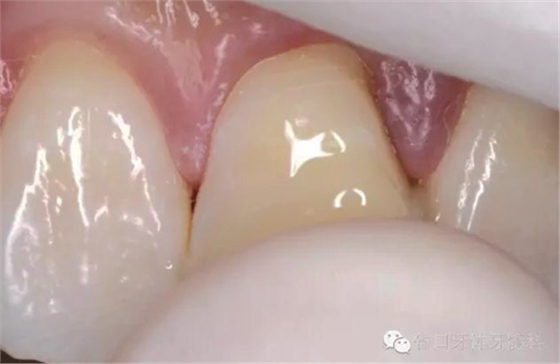

術后即刻口內照

口內檢查:21切端牙體色澤恢復,唇側面見水平向粘接界面,殘留少許樹脂水門汀,牙齦腫脹較前消退,叩-,松-。

處理:21唇側沿粘接界面磨除少量牙釉質,